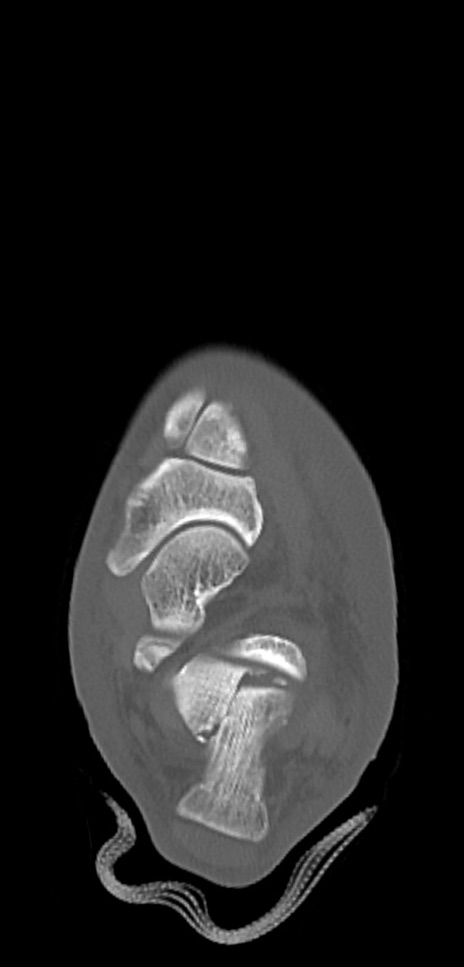

症例37 左足関節CT(横断像)

左足関節CT